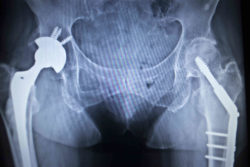

A man has filed a Stryker hip system lawsuit after he had to undergo explantation of the LFIT V40 femoral head.

Plaintiff Charles R. said he received a Stryker hip replacement in his right hip in November 2008. The surgery included the implantation of a Stryker LFIT Anatomic CoCr V40 femoral head and the Stryker Accolade TMZF femoral stem.

Charles allegedly had the LFIT V40 femoral head removed in September 2017 after purportedly suffering severe injuries from the components of the Stryker hip system.

The metal-on-metal Stryker hip system implanted in Charles included a cobalt and chromium LFIT V40 femoral head. The Accolade TMZF femoral stem was made of a proprietary alloy that Stryker advertised as a stronger stem compared to femoral stems made of other metal alloys.

Stryker marketed the LFIT V40 femoral head to be used with the Accolade TMZF femoral stem, advocating that when the two were mated, the patient would experience maximum hip mobility with a decreased chance of dislocation.